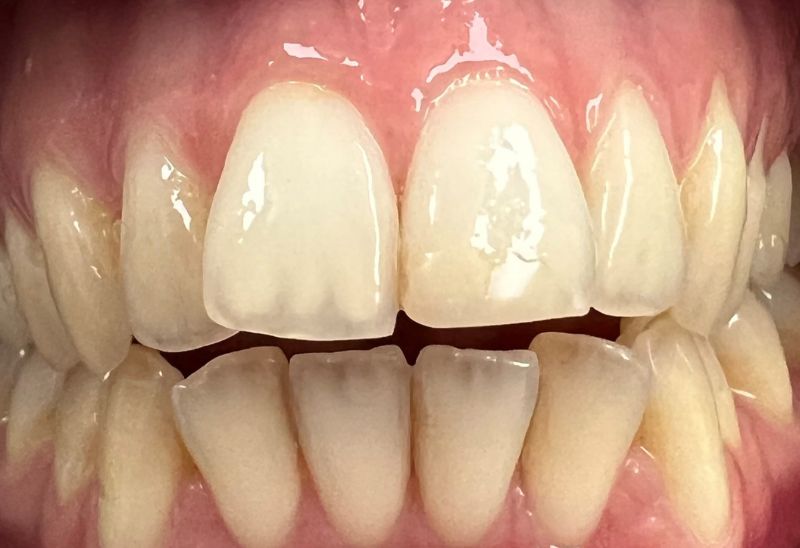

Prima e dopo l'apparecchio invisibile

In questa sezione mostreremo risultati reali ottenuti con l’ortodonzia invisibile a Roma. I cambiamenti riguardano non solo i denti, ma anche l’armonia del viso, la postura orale e l’autostima.